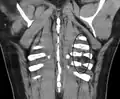

Radiographie de multiples fractures costales gauches (entourées d'un ovale)